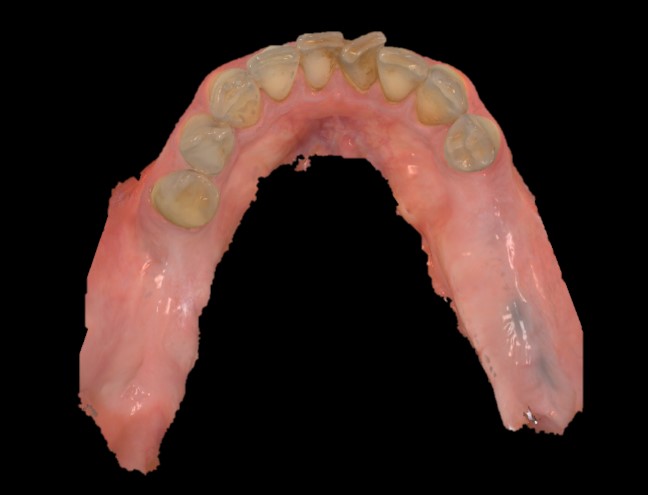

Il paziente, in buono stato di salute generale, si presentava con un’edentulia dei settori posteriori dell’arcata mandibolare. In particolar modo, all’esame obiettivo, si evidenziava l’assenza di tutti i molari inferiori e del secondo premolare di destra (Figure 1,2). Il paziente riferiva la perdita degli elementi dentali da qualche anno per motivi di carie e fratture, inoltre diceva di non aver mai provveduto ad una nuova riabilitazione principalmente per mancanza di tempo, a causa dei tanti impegni di lavoro. Si pianificava quindi una riabilitazione implantare degli elementi 45-46 e 36, da eseguire in chirurgia guidata in un’unica seduta, e con l’inserimento di nuovo tipo di abutment di guarigione chiamato Profile Designer iPhysio® (Lyra ETK, Sallanches, Francia) in grado di ridurre i tempi legati alle fasi di protesizzazione degli impianti.

Fig. 1. Foto che mostra l’edentulia dei settori posteriori mandibolari.

Fig. 2. Scansione intraorale.